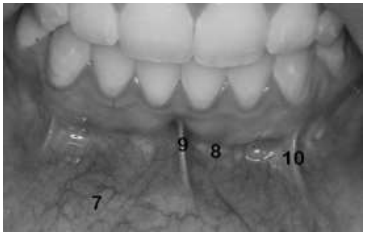

INSTRUÇÃO: Considere a imagem a seguir para responder a questão:

As estruturas apontadas em 7 e 8 representam, respectivamente:

Fórnice do vestíbulo e Mucosa labial.

Mucosa labial e Fórnice do vestíbulo.

Freio lateral e Mucosa alveolar.

Mucosa alveolar e Freio lateral.